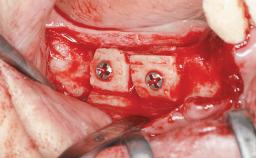

A 47-year-old woman who had suffered from aggressive periodontitis requiring a number of periodontal interventions over more than 10 years was referred by her general dental practitioner and periodontologist for bone augmentation and implant therapy. Her failing dentition had already been scheduled for extraction. The patient expressed a desire for implant-supported fixed restorations and esthetic improvement of her lower face. She had agreed to consult with a maxillofacial surgeon after the referring dentist had suggested bone augmentation. An initial examination by the maxillofacial surgeon revealed mobility of all residual teeth in a patient who was very unhappy with the function of her removable partial dentures. Due to periodontally migrated flaring teeth and loss of occlusal support, the vertical dimension of occlusion was dramatically reduced. The patient was displeased with her lower face because of deepened nasolabial, commissural, and supramental folds.

Bone Augmentation Horizontal|Sinus Floor Elevation|Staged|Vertical

Augmentation Materials Autogenous chips|Autogenous block(s)|Xenogenous|Membrane

Bone Volume Deficient vertically or deficient vertically AND horizontally